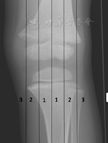

术后6周、3个月及半年时复查拍摄股骨或胫骨正侧位X线片,截骨愈合后每年拍摄一次双下肢全长正位及膝关节正侧位X线片。在双下肢全长正位片上测量患肢的股骨远端机械轴外侧角(mLDFA)、胫骨近端机械轴内侧角(mMPTA)、机械轴线与膝关节中心点间的偏移距离(MAD)及胫骨平台后倾角,记录患儿术前膝关节活动度(ROM)。对于最终的矫正效果,按照Stevens等[5]的膝关节分区方法评价(图2),下肢机械力线通过膝关节位置为1区的认为矫正效果优异,2区的认为矫正效果良好,3区为效果欠佳。

注:1区为内外侧中央1/4,2区为内外侧边缘1/4,3区为膝关节边缘以外